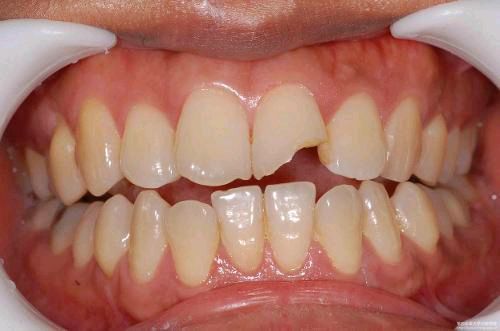

意外的牙齿外伤后应该怎么办 牙齿外伤是指牙齿受到急剧创伤,特别是打击或撞击伤所引起的牙体、牙髓和牙周组织损伤。一般分为:牙齿震荡,包括牙周损伤、牙髓损伤、牙体损伤;牙齿折断,包括牙冠折断、... 补牙 谬长逸 672 2023-11-25